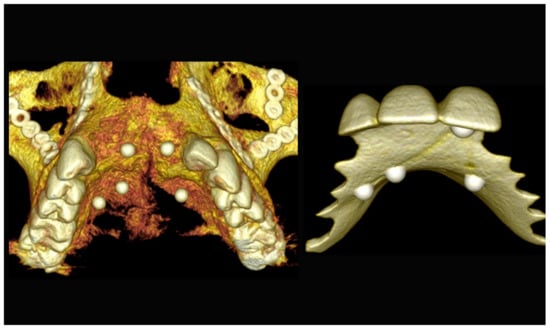

The number, the length, the diameter and the placement of computational virtual implants were determined with respect to the design of the final prosthesis the available residual bone volume and the anatomical limitations according to the previously described technical procedure (Figure 31, Figure 32, Figure 33 and Figure 34).

Figure 31.

Three-dimensional (3D) CBCT scan images of the edentulous mandible with the patient wearing the provisional prosthesis and 3D images of the prosthesis equipped with integrated radiopaque reference spheres scanned separately.

Figure 32.

Planning of the number, the diameter, the axis of the implants with respect to the design of the final prosthesis and the trajectory of the inferior alveolar nerves.